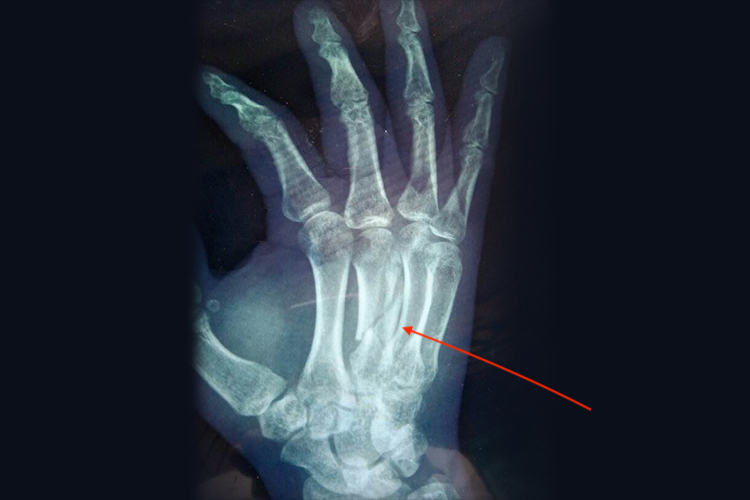

手背骨折多指掌骨骨折,主要表现为骨折部位有肿胀、疼痛、压痛、畸形和活动受限,多因暴力导致,损伤部位不同,治疗不同。

手背骨折主要表现为疼痛,患侧手局部肿胀,关节处瘀肿,活动受限,压痛或纵轴叩痛。功能障碍表现为第1掌骨基底部骨折,第1掌腕关节处活动障碍。掌骨干骨折,掌骨中段瘀肿,压痛及纵轴叩痛,骨折端常向背侧成角及向侧方移位。掌骨颈骨折,掌指关节畸形,掌指关节过伸,掌骨头向掌侧屈曲。掌骨头骨折,掌指关节瘀肿,压痛,掌指关节活动障碍。

手背骨折若无错位,需遵医嘱进行固定恢复,若出现移位现象,需遵医嘱使用手法或牵引复位,之后进行固定,若手法复位失败,可行手术切开复位及内固定术。固定拆除后,还需进行适度的功能锻炼,有利于手部功能的恢复。